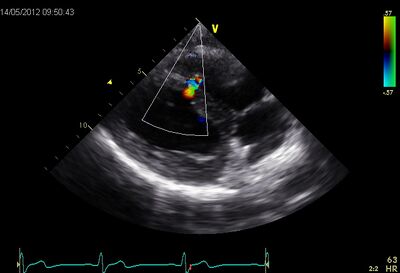

VSD.jpg VSD02.jpg

Muscular VSD tilted by PLAX Muscular VSD Subcostal 4CH